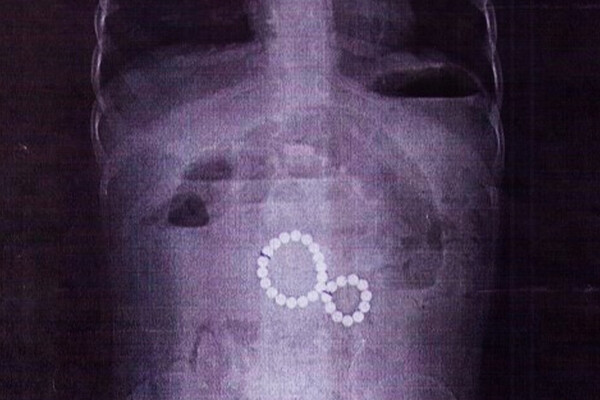

Двухлетний ребенок проглотил 29 магнитных шариков — при каких обстоятельствах это случилось, не уточняется. В больницу девочка поступила в тяжелом состоянии с симптомами кишечной непроходимости и кровавой рвотой. Рентген показал, что магниты, попав в разные отделы кишечника, создали опасное сцепление, что привело к внутренней грыже и угрозе разрыва стенки кишки.